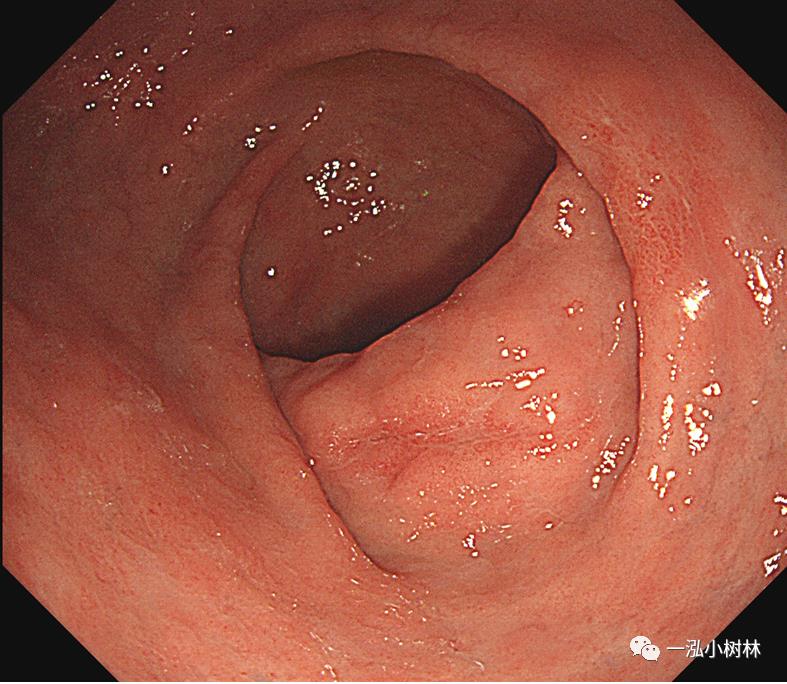

例6 胃体上部病变

图6 白光内镜:胃体上部高分化腺癌,ESD病理提示黏膜下浸润(>500um)。